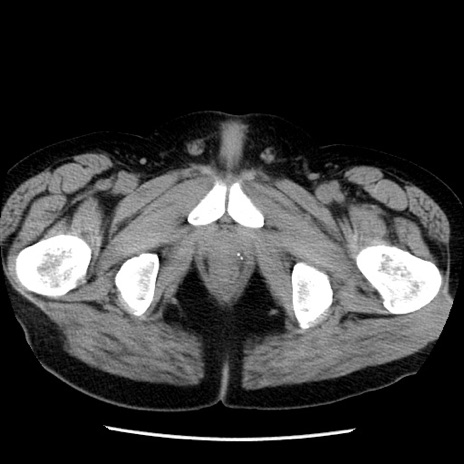

冠状断像

【症例】40歳代男性

【現病歴】2日前から胃痛あり。徐々に周期的な激痛に変化した。本日になっても激痛があるため受診。

【身体所見】意識清明、BT 38-39℃台あり、腹部:膨満、やや硬、右下腹部に圧痛あり。

【データ】WBC 8500、CRP 23.26